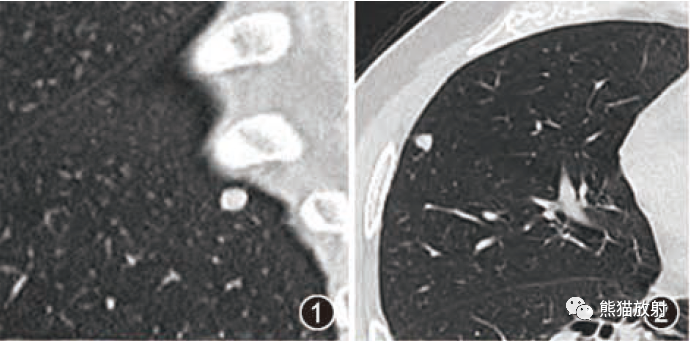

迅速增大的肺部结节,首先考虑良性,确诊需要肺穿  肺隔离症:易误诊为肺癌的占位性病变,肺穿刺禁忌!